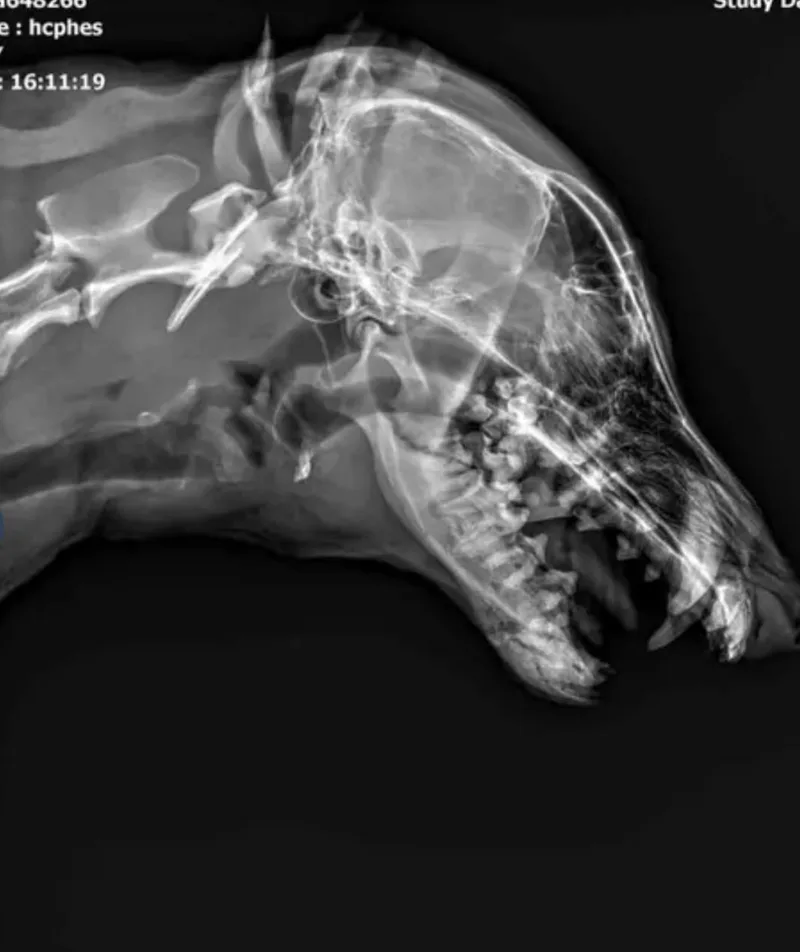

Micaela’s Journey to Healing 💙 Micaela didn’t arrive at the shelter with a wagging tail or bright eyes. She arrived in pain—quiet, hurting, and trying her best to be brave. At only about 2 years old, this young husky had already endured more suffering than most dogs face in a lifetime. She was taken to a Texas high‑kill shelter, where her severe injuries and silent agony nearly cost her life. A veterinary exam revealed what her gentle spirit had been hiding: a fractured jaw, significant misalignment, and bleeding gums. Every attempt to eat, drink, or simply rest caused her pain. Without urgent medical care, her future looked heartbreakingly grim. But Micaela’s story didn’t end there. Hoardin’ Huskies stepped in just in time, wrapping her in the compassion she had been denied for far too long. We rushed her to NVC in Nederland, TX, where Dr. Hanson began the care she desperately needed. After a full evaluation, we learned her jaw fractures were very old—left untreated long enough to cause deep tissue infection and several dead teeth. Re‑breaking and resetting her jaw wouldn’t help her now. What she needed was relief, real relief, through a full dental cleaning and removal of the damaged teeth. And that’s exactly what she’s getting. On top of everything, Micaela is also heartworm positive, but she has already begun slow‑kill treatment, giving her a safe and steady path toward full recovery. The best news of all? Micaela will be able to live a completely normal, pain‑free life. Even now, as she begins her healing journey, her resilience is shining through. She leans into gentle touch. She watches her caregivers with soft, grateful eyes. She is learning—slowly, bravely—that she is finally safe. It’s almost unbearable to imagine what she endured before help arrived. She survived pain, neglect, and fear. She survived a high‑kill shelter where her injuries nearly cost her life. But she didn’t give up. And because of that, she now has a real chance at comfort, love, and the peaceful life she always deserved. And now, for the first time in her young life, Micaela is officially available for her forever home—a home where she will never again be overlooked, unheard, or in pain. A home where her gentle heart can finally rest. Micaela’s story is one of quiet strength, second chances, and the power of compassion. Her healing has begun, and her future is finally filled with hope. Who can give this sweet girl a forever home where she will always know she is now loved. http://hoardinhuskies.net/dog-adoption/